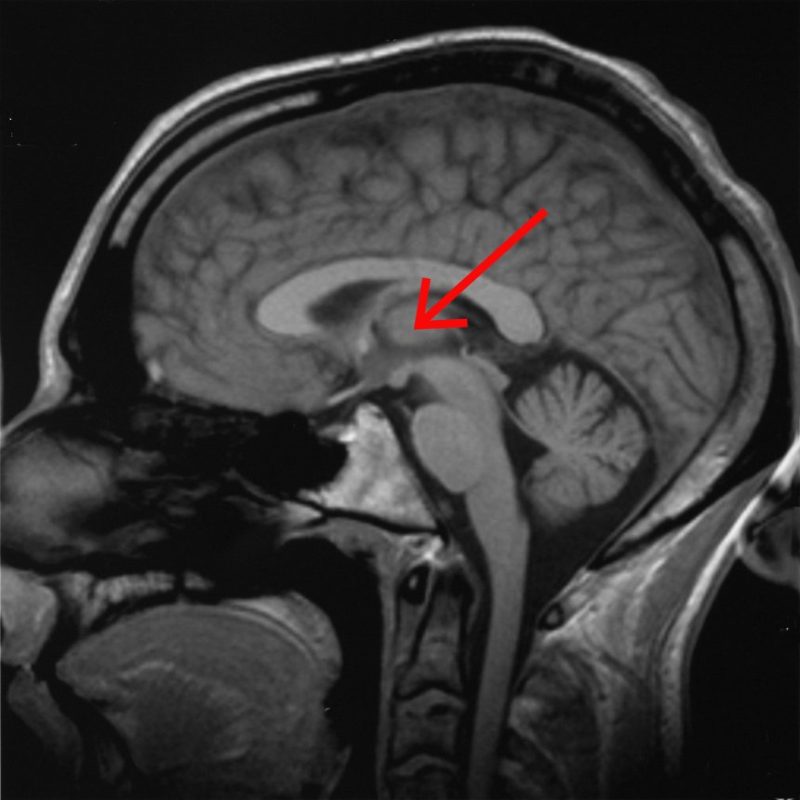

আসলে আমাদের মস্তিষ্কের “সেরিব্রাল কর্টেক্স” ও “থ্যালামাস” অংশদুটির সংযোগকারী যে নিউরাল লুপগুলিতে গামা তরঙ্গ বয়ে চলে সেগুলি আমাদের মস্তিষ্কে সংগৃহীত দৃষ্টি, শব্দ, ও ভাষা সম্বন্ধীয় তথ্যগুলি থেকে স্থানিক উপাংশকে নিষ্কাশন করে; এবং গামা তরঙ্গ বহনকারী যে নিউরাল লুপগুলি “সেরিব্রাল কর্টেক্স”-র সাথে “মিডব্রেইন” অংশকে সংযুক্ত করে সেগুলি সংগৃহীত তথ্যগুলি থেকে সময়গত উপাংশকে বেছে দেয়।

থ্যালামাস